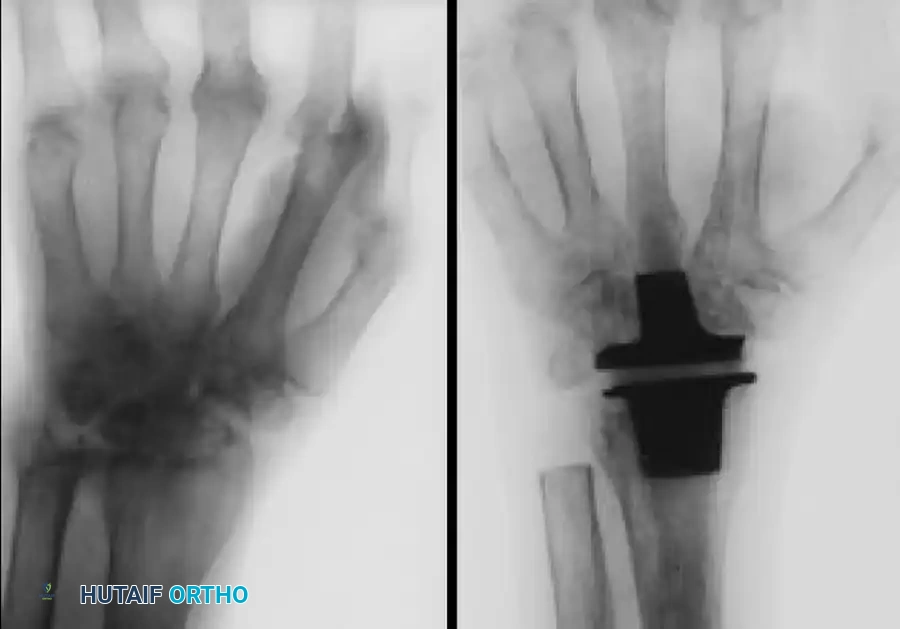

Image

FIGURE 73-46 A & B: (A) Preoperative radiograph of a wrist affected by severe rheumatoid arthritis demonstrating profound carpal collapse and radiocarpal disease. (B) Postoperative radiograph obtained after replacement of the wrist joint with a Swanson silicone implant and titanium grommets.